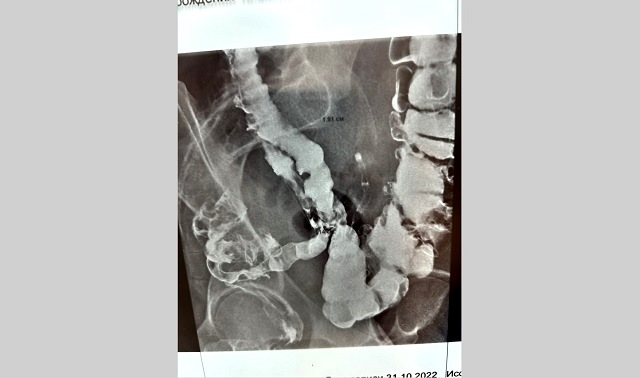

«И только в 7 горбольнице, проведя ренгенконтрастное исследование кишечника, не только нашли этот очаг эндометриоза, но и установили, что он сужает просвет кишки, — рассказала научный куратор гинекологов клиники Рушанья Габидуллина.

Пациентке требовалась мультидисциплинарная помощь, с участием хирургов и гинекологов, которая была оказана в нашей больнице. Пациентка тоже съездила на консультацию в Москву и вернулась в Казань.

«Первичное поражение кишечника (при отсутствии эндометриоза в других органах, из которых он мог бы распространяться в кишку) наблюдается редко и происходит в результате гематогенного, т. е. с током крови, занесения клеток, похожих на эндометрий, в стенку кишки.

Именно такой случай и был у нашей пациентки. Эндометриоз себя проявил первичным поражением толстой кишки, что встречается редко в практической деятельности хирургов», — пояснили медики.